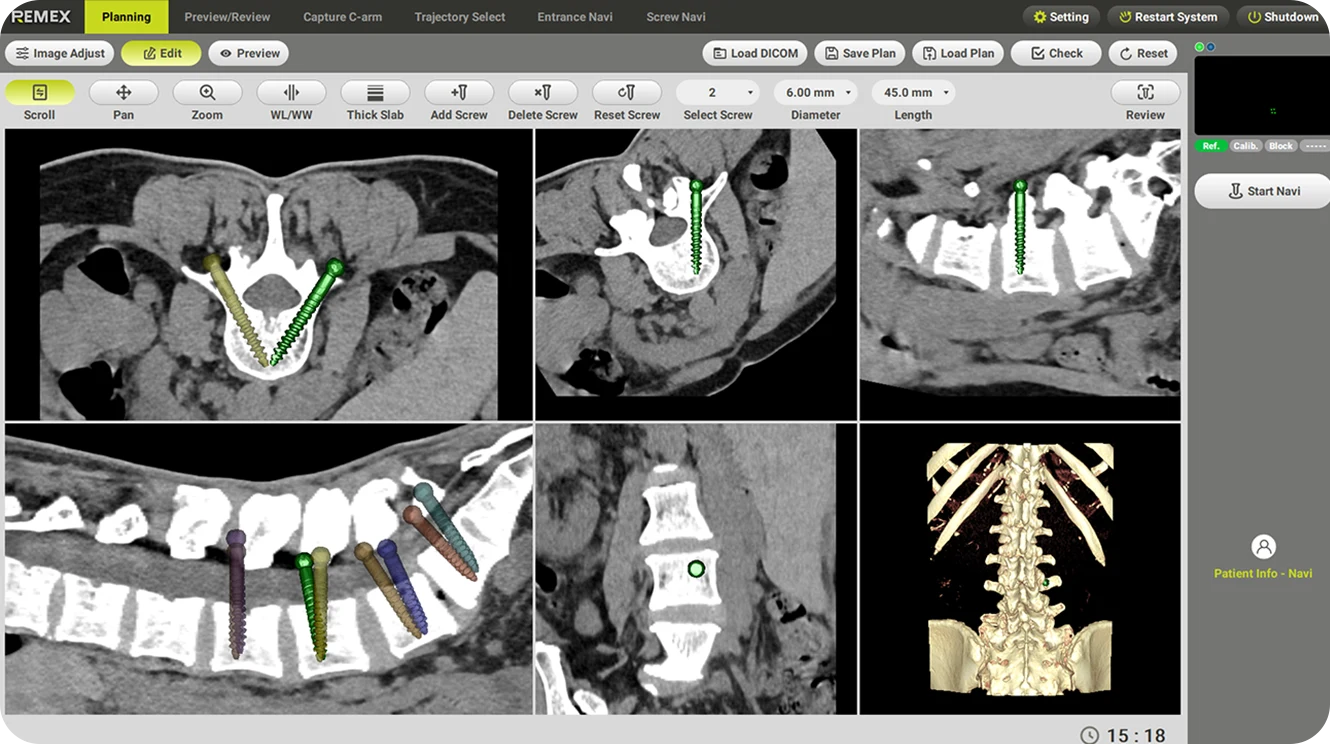

Planificación quirúrgica

Ajusta la posición y la profundidad del tornillo basándote en las imágenes de TC preoperatorias.

Planeación de trayectorias opcionales

Ofrece funciones opcionales de planificación de trayectorias preoperatorias e intraoperatorias para visualizar la colocación del implante y maximizar el aprovechamiento del quirófano.

Registro 2D y 3D

La tecnología central mejora la precisión y seguridad con un tiempo de configuración rápido. Basado en imágenes de CT preoperatorias y dos imágenes de rayos X intraoperatorias, el algoritmo avanzado de imágenes y el software de reconstrucción completan el registro de manera eficiente.

Navegación 3D en tiempo real

Después de una verificación sencilla de los instrumentos, estos junto con los implantes se visualizarán claramente en tiempo real. La posición relativa de todos los dispositivos y del paciente estará bajo control y se mostrará en visores de imagen únicos para distintos procedimientos quirúrgicos.